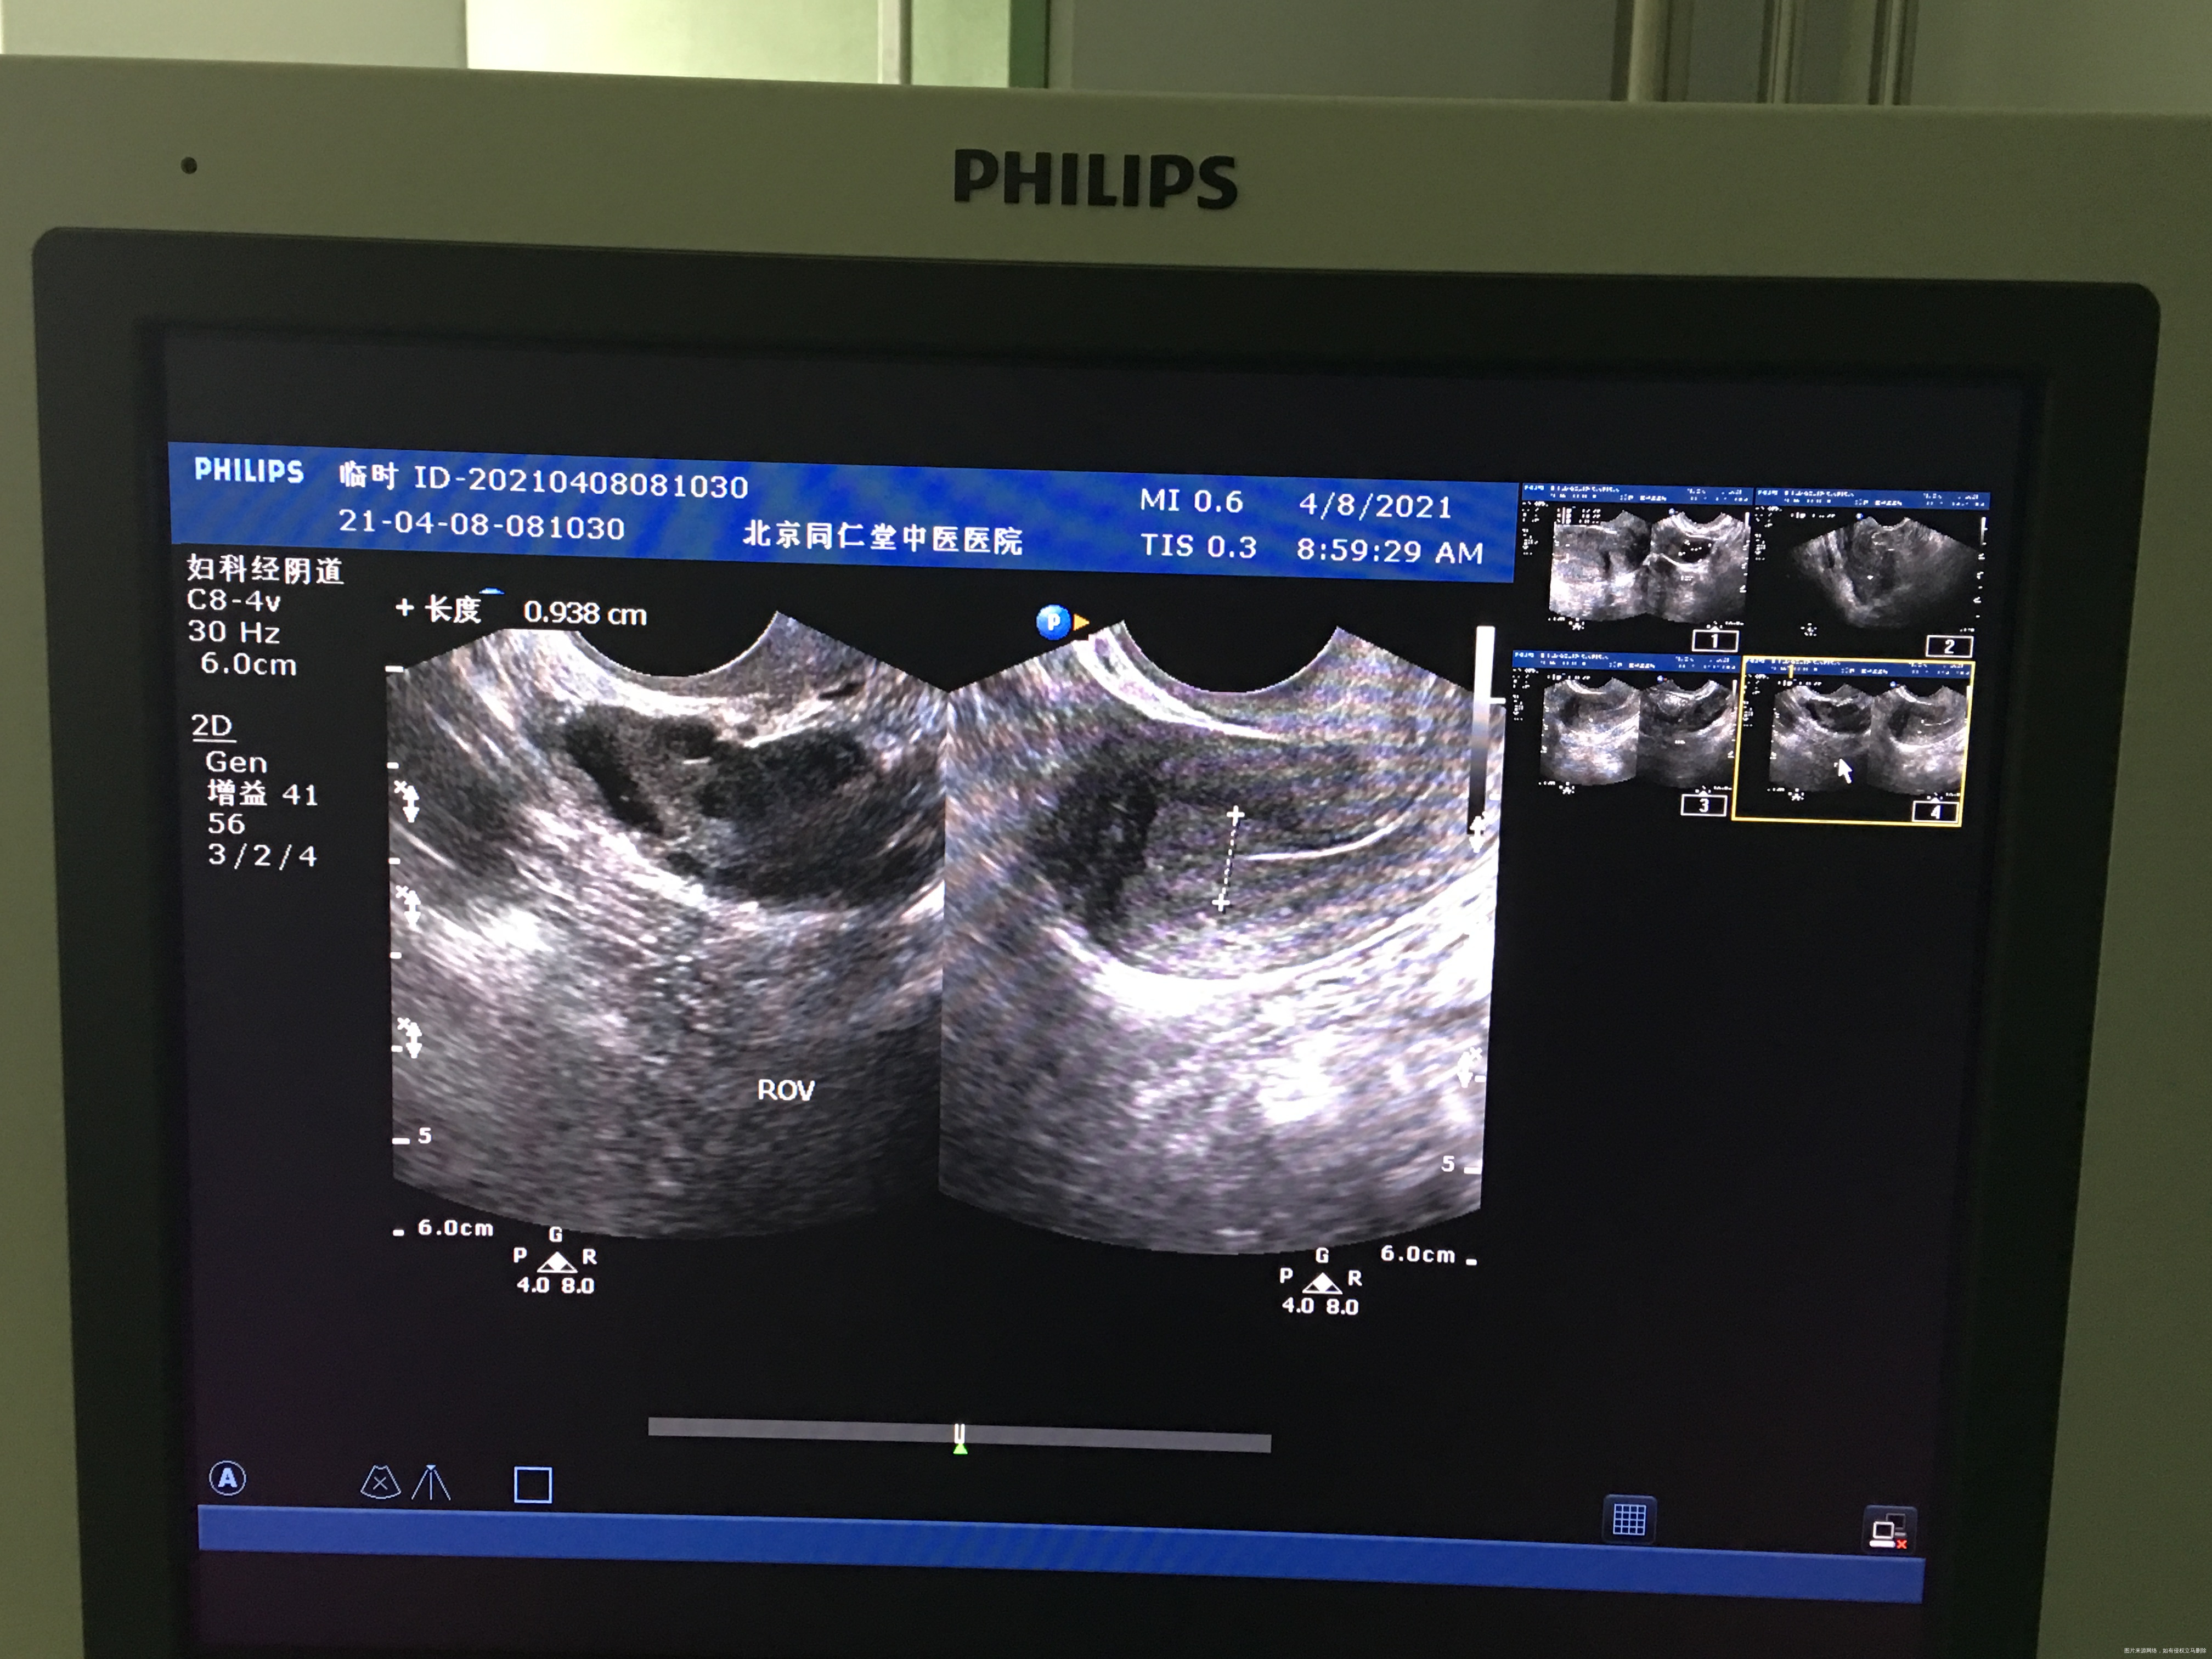

您好,我月经不规律,上次月经3.月2日,请问我现在这个b超显示已经排卵了吗?现在内膜是0.93

你好,根据这个B超没看出来是否已排卵,我只看到卵泡比较多,你应该是有点多囊卵巢,建议医院就诊全面评估治疗!

你好!内膜厚度可以,没有排卵迹象。继续检测卵泡看看。

排卵期内膜厚正常,和卵泡发育不一定同步。成熟大卵泡,排卵后会有一些特征,比如宫腔有少量积液,卵泡膜张力变化等,你的情况不明显,明天再做b超,比较下。

根据B超看不出是否已排卵,排卵后形成黄体,但是很多医院不报告黄体,内膜厚度可以,你可以测个血孕酮值看看,孕酮值大于5考虑已排卵。